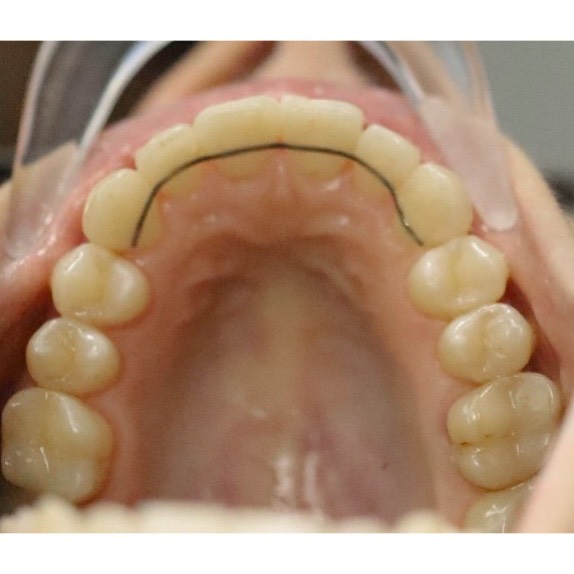

Как я исправила прикус за 2 года? История с элайнерами

Делюсь сложным кейсом лечения на элайнерах длиной в 2 года и 1 месяц.

Потребовалось удаление всех восьмерок и терпение пациента к улыбке своей мечты. Мы очень довольны результатом.